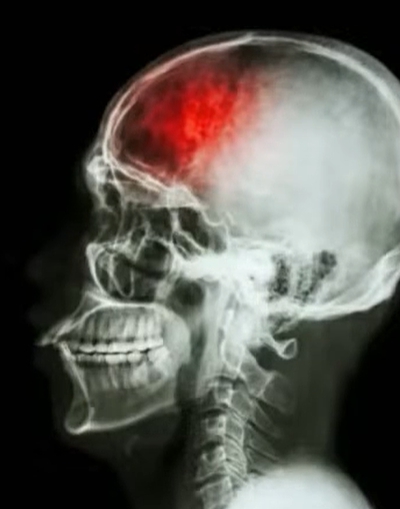

서론 | 뇌경색 전조증상, 그냥 지나치기 쉬운 몸의 경고 신호

뇌경색은 갑자기 쓰러지는 병으로 생각하기 쉽지만, 실제로는 발병 전 며칠 또는 몇 주 전부터 뇌경색 전조증상이 반복적으로 나타나는 경우가 많습니다. 문제는 이 신호들이 피로, 스트레스, 혈압 문제 정도로 오해되어 그냥 넘겨진다는 점입니다. 하지만 이 시기를 놓치면 몇 분, 몇 초 사이에 평생 후유증으로 이어질 수 있기 때문에, 미리 알고 대처하는 것이 무엇보다 중요합니다.

📌 전조증상이 왜 생길까? — 뇌혈류가 ‘잠깐’ 막혔다가 풀리는 상태

뇌경색 전조증상은 뇌혈관이 완전히 막히기 전, 혈전이나 혈관 수축으로 일시적으로 혈류가 줄어드는 상태에서 발생합니다. 이때 뇌세포는 잠깐 기능을 멈췄다가 다시 회복되기 때문에 증상이 사라지는 것처럼 보입니다. 하지만 혈관 상태가 그대로라면, 다음에는 완전히 막히면서 실제 뇌경색으로 이어질 위험이 매우 높습니다. 특히 다음 조건에 해당하면 전조증상 발생 위험이 더 높아집니다.